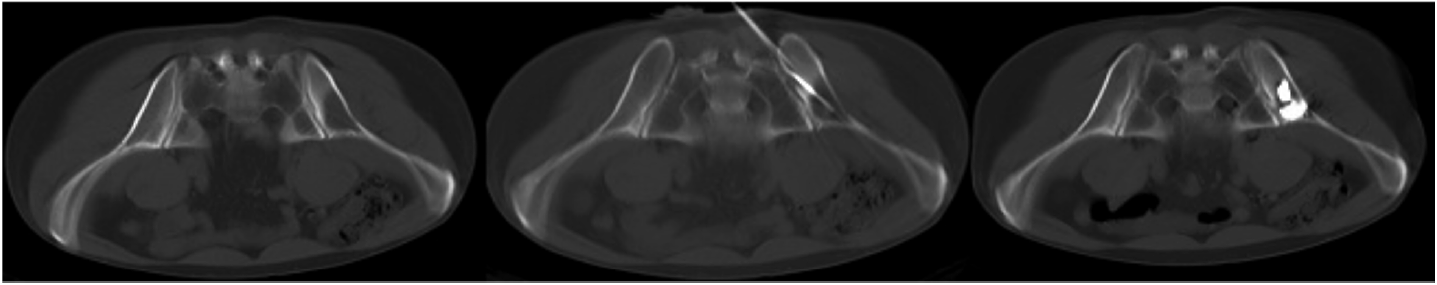

Остеопластика выполнена 38 пациентам и заключалась во введении полиметилметакрилата (костного цемента) в очаг деструкции костной ткани под контролем КТ с целью снижения БС и/или профилактики патологического перелома. Средний объем введенного костного цемента составил 6 мл (от 4 до 10 мл); рис. 3.

Рис. 3. КТ костей таза до проведенного лечения, во время РЧТА и после выполненной остеопластики. Литический компонент метастатической опухоли практически полностью заполнен костным цементом.

Fig. 3. CT of pelvic bones before the treatment, during RFA and after the osteoplasty. The litic component of the metastatic tumor is almost completely filled with bone cement.

РЧТА выполнена 13 больным при наличии экстраоссального мягкотканого компонента в пораженном костном сегменте с деструкцией кортикального слоя, который не позволял добиться обезболивающего эффекта только введением костного цемента в очаг поражения. Операция выполнялась под контролем КТ, при этом в центр опухолевого очага вводили радиочастотный электрод с проведением локальной гипертермии данного очага свыше 70°С в течение 8–12 мин. Далее, если литическая деструкция располагалась в крыше вертлужной впадины, дополнительно вводился костный цемент.